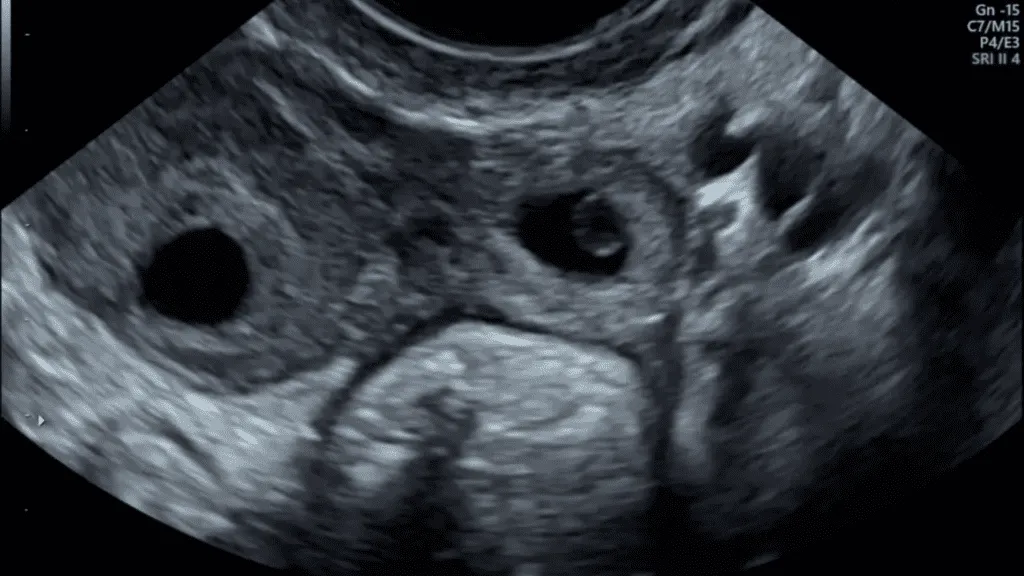

Fallopian Tube:আজকাল অনেক মহিলা বন্ধ্যাত্বের সমস্যার সম্মুখীন হচ্ছেন। বার্ধক্য, অস্বাস্থ্যকর জীবনধারা, অতিরিক্ত ওজন এবং পিসিওডির মতো কারণগুলি মা হওয়ার পথে বাধা তৈরি করে। এর সঙ্গে এটি প্রকাশ পেয়েছে যে অনেক মহিলার মধ্যে ফ্যালোপিয়ান টিউব ব্লকেজের সমস্যাও দেখা দিচ্ছে।